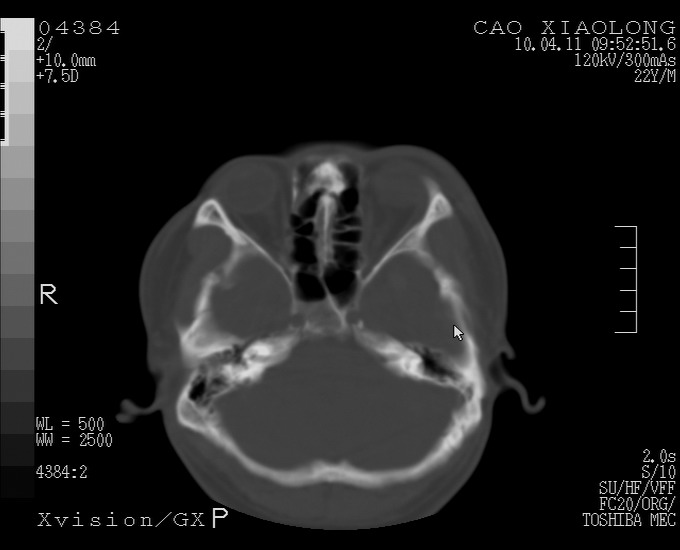

以下是引用随光逐影在2010-4-11 11:00:00的发言:[br]1)左侧额颞顶部硬膜下血肿。2)蛛网膜下腔出血。3)右侧颞顶部颅骨线形骨折。[br][br]20小时后复查:左侧额颞叶脑挫裂伤;左侧额颞顶部硬膜下血肿及蛛网膜下腔出血有吸收表现;右侧颞顶部颅骨线形骨折。[br]